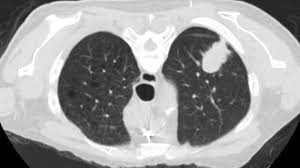

Can You Detect Lung Cancer With Ct Scan - Detection Of Early Stages Of Lung Cancer Based On Imaging A Download Scientific Diagram - Your doctor might use imaging tests to look for unusual growths inside your body that might be cancer.. It can also show whether the cancer has spread outside the lung. It gives detailed information about your cancer. Ct scans of the chest are used to find lung nodules or other chest pathology. Therefore, ct scans can lead to a false negative this can negatively impact your ability to get any treatment at all If cancer is diagnosed, other tests will be performed to stage and grade the tumor so that the appropriate treatment can be delivered.

A ct scan test can also be used to look for the spread of lung cancer in the adrenal. Once a nodule is found, a workup is done to see if it is cancer. It is used to look for early signs of lung cancer. Ct scans of the chest are used to find lung nodules or other chest pathology. Awareness of the possible causes of overlooking a pulmonary lesion can give radiologists a chance to reduce the occurrence of this eventuality. This can provide definitive evidence of the disease. If you are a smoker, it is highly recommended to have a ct scan every 3 months. It gives detailed information about your cancer. It's equal to about half the radiation you're exposed to naturally from the environment in a year. Another doctor might be able to recommend other testing options. Your doctor might use imaging tests to look for unusual growths inside your body that might be cancer. Computed tomography (ct) scans detect tumors, but do not determine whether they are malignant or not. The doctor will then order additional testing to rule out or confirm a cancer diagnosis.

But the test is not helpful for light smokers or people who quit smoking more than 15 years ago. Early detection of lung cancer means more treatment options an excellent tool for people at high risk for lung cancer the scan is quick, painless and noninvasive ct imaging is detailed and accurate and can reveal the smallest of abnormalities The scan looks at your lungs and other parts of your chest. Ct is highly accurate for lung cancer detection. Nevertheless, lung cancer can also be overlooked on computed tomography (ct) scans, regardless of the context, either if a clinical or radiologic suspect exists or for other reasons. A ct scan test can also be used to look for the spread of lung cancer in the adrenal. If you are at higher risk, talk to your doctor about getting screened. The smallest recesses of the chest can be clearly seen. It can also show the size, shape, and position of any lung tumors and can help find enlarged lymph nodes that might contain cancer that has spread. Therefore, ct scans can lead to a false negative this can negatively impact your ability to get any treatment at all Ct scans of the chest are used to find lung nodules or other chest pathology. Alternatively, you should take lung ct scans if you are concerned or if you show any symptoms. It can also look at your liver and adrenal glands.

Ldct scans can help find abnormal areas in the lungs that may be cancer. It can also look at your liver and adrenal glands. It can show the size, shape, position, and depth of any lung tumor. Nevertheless, lung cancer can also be overlooked on computed tomography (ct) scans, regardless of the context, either if a clinical or radiologic suspect exists or for other reasons. Ct is highly accurate for lung cancer detection.